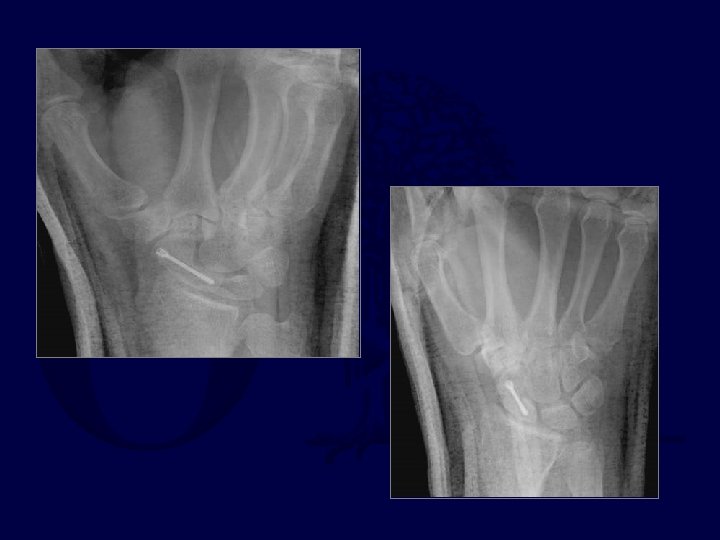

Trans-scaphoid Perilunate Dislocations

Fix scaphoid first: dorsal approach

Pin L-T and Mid-carpal joints

Make sure Radius -Lunate-Capitate are colinear and S -L angle restored

Scaphoid healing